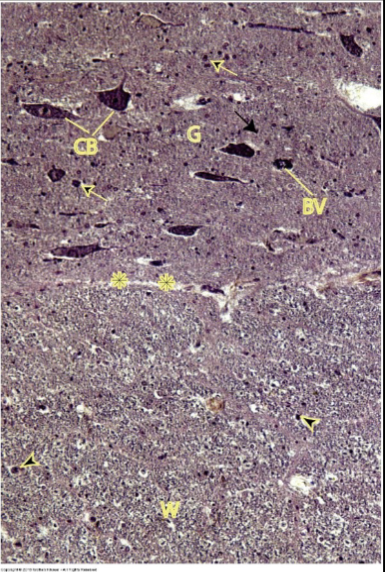

in the Spinal cord, what does its Grey matter contain?

somas of multipolar neurons & neuroglia nuclei

in the Spinal cord, what does its White matter contain?

collection of myenlinated axons w/ neuroglia nuclei